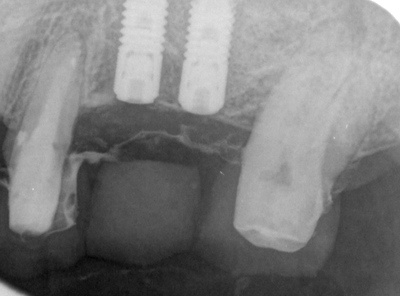

HOME > ブログ 一覧 > 左上56部へのサイナスリフトを伴うインプラント治療 2020.01.28左上56部へのサイナスリフトを伴うインプラント治療 左上56部2本欠損部へのインプラント。 術前写真。 術前CT。 インプラント治療行うには全く骨が不足している。 ラテラル法によるサイナスリフトを行い、インプラントを同時埋入。 使用インプラントはアストラEV。 間隔が狭いため、細めのインプラント2本で対応した。 術後。 骨が移植されているのが分かる。 複雑、難症例は当院の得意とするところです。 Recent Entries アライナー矯正(インビザライン、シュアスマイル)費用を2023年 1月から改訂させていただきます(01/09) 本年もよろしくお願いいたします(01/02) 年始の診療について(01/01) 新しいWEBへ移行、年末年始の診療のお知らせ(12/29) ダラダラ根管治療行っても治らないという事(12/21) Category その他の治療(126) インビザライン・矯正(52) インプラント治療(216) ホワイトニング(47) メインテナンス(21) 包括診療(95) 医院からのお知らせ(249) 審美治療(128) 日々雑感(283) 根管治療(100) 歯周病治療(90) 矯正(73) 補綴治療(45) 補綴治療カテゴリを追加(1) 診療全般(44) Archive 2023年1月(3) 2022年12月(6) 2022年11月(14) 2022年10月(6) 2022年9月(8) 2022年8月(7) 2022年7月(13) 2022年6月(8) 2022年5月(7) 2022年4月(7) 2022年3月(6) 2022年2月(7)